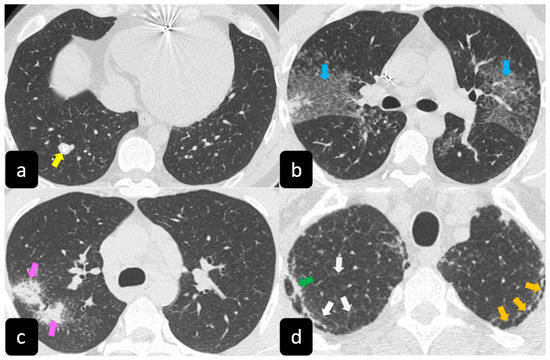

2.2. Typical and Atypical Manifestation of Pulmonary Sarcoidosis at HRCT

3.2. HRCT Findings of Lung Involvement from COVID-19